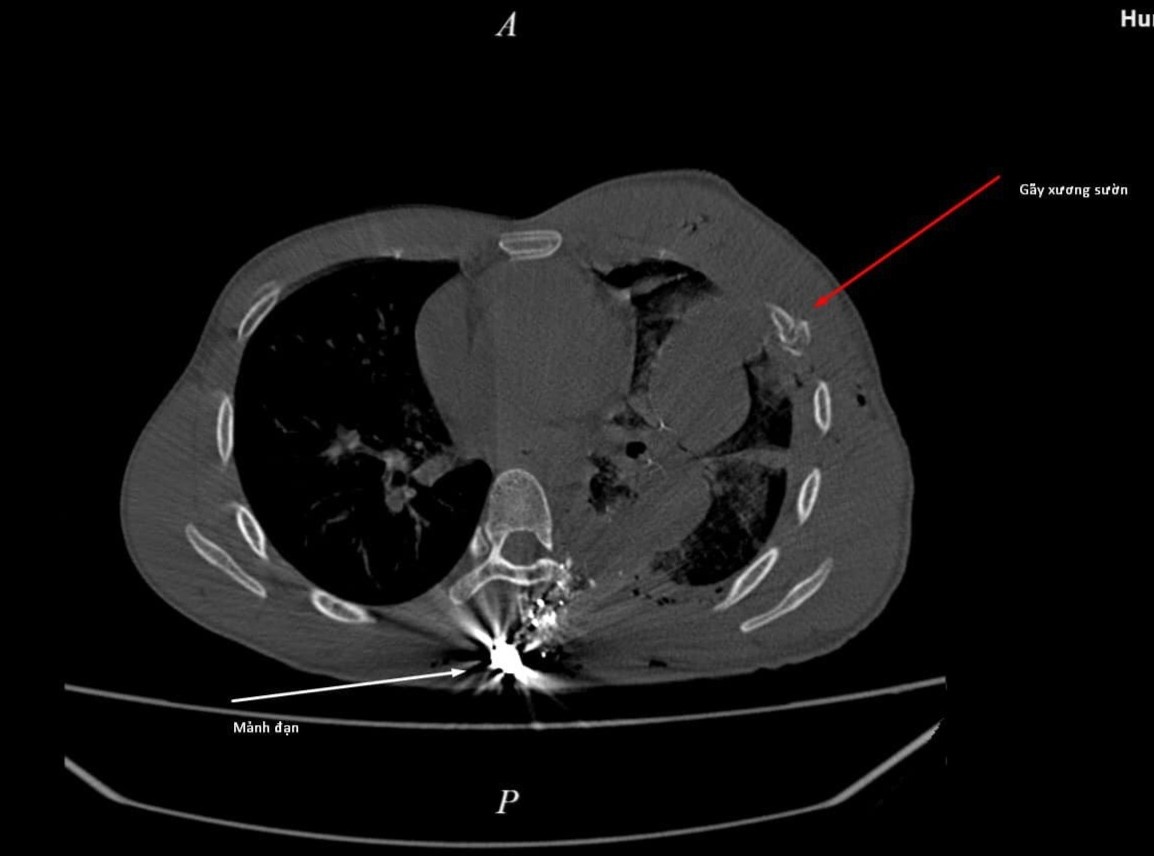

Người đàn ông ở Hà Giang bị mảnh đạn đâm xuyên thành trước ngực, gây chảy máu, tràn dịch màng phổi trái, gãy xương sườn.

Kết quả chụp cắt lớp cho thấy bệnh nhân bị gãy xương sườn, mảnh đạn vẫn nằm trong cơ thể. Ảnh: BVCC.

Kết quả chụp cắt lớp vi tính ngực cho thấy mảnh đạn đâm xuyên thành trước ngực, qua phổi và vẫn nằm trong cơ thể bệnh nhân.